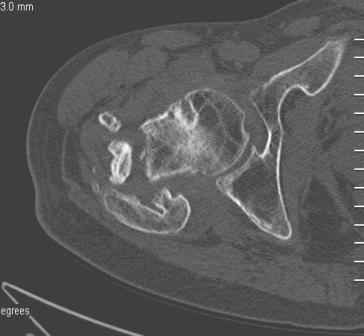

Больной Н. 44 года травма 1,5 года назад июнь 2008 года чрез-под вертельный перелом правого бедра. Во время лечения у больного развился алк. делирий, проводилось консервативное лечение перелома.

Беспокоят боли, укорочение конечности.Укорочение 3 см. Ногу поднимает, сгибание ограничено, ротационные движения в полном объеме.На КТ перелом сросся за счет костной мозоли.Что делать?

Уважаемый Глеб! Укорочение наверное побольше, да и наружно-ротационная установка скорее всего присутствует. Суставная щель прекрасная, головка живее всех живых. Ратую за подвертельную с латерализацией: исключает нарушение механической оси («исключает вальгус в коленe»), максимально удлиняет без натяжения m.iliacus. Для иллюстрации остеотомия-переделка (слава богу не автопеределка) у мужчины 65 лет.